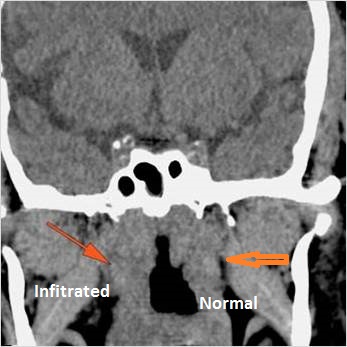

There is infiltration of the fat surrounding the nasolacrimal sac either preseptal or postseptal. [Yes/No]

There is soft tissue infiltration or bone erosion along the nasolacrimal fossa or canal. [Yes/No]